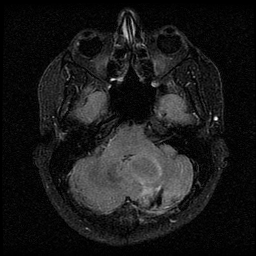

![]() |

| (a) | (b) | (c) | (d) |

Unsupervised Categorization: Our category discovery clusters are generally visually coherent within the cluster and size-balanced across clusters. However, image clusters formed only based on text information (of radiology reports) are highly unbalanced [49], with three clusters inhabiting the majority of images. Note that our method imposes no explicit constraint on the number of instances per cluster. Fig. 6 shows sample images and their top-10 associated key words from two randomly selected clusters (more results are provided in the supplementary material). The LDPO clusters are found to be clinically or semantically related to the corresponding key words, which describe presented anatomies, pathologies (e.g., adenopathy, mass), their associated attributes (e.g., bulky, frontal) and imaging protocols or properties.

The category discovery clusters employing our LDPO method are found to be more visually coherent and cluster-wise balanced in comparison to the results in [49] where clusters are formed only from text information ( radiology reports). Fig. 7 Left shows the image numbers for each cluster from the AlexNet-FC7-Topic setting. The numbers are uniformly distributed with a mean of 778 and standard deviation of 52. Fig. 7 Right illustrates the relation of clustering results derived from image cues or text reports [49]. Note that there is no instance-balance-per-cluster constraints in the LDPO clustering. The clusters in [49] are highly uneven: 3 clusters inhabit the majority of images. Fig. 6 shows sample images and top-10 associated key words from 5 randomly selected clusters (more results in the supplementary material). The LDPO clusters are found to be semantically or clinically related to the corresponding key words, containing the information of (likely appeared) anatomies, pathologies (e.g., adenopathy, mass), their attributes (e.g., bulky, frontal) and imaging protocols or properties.